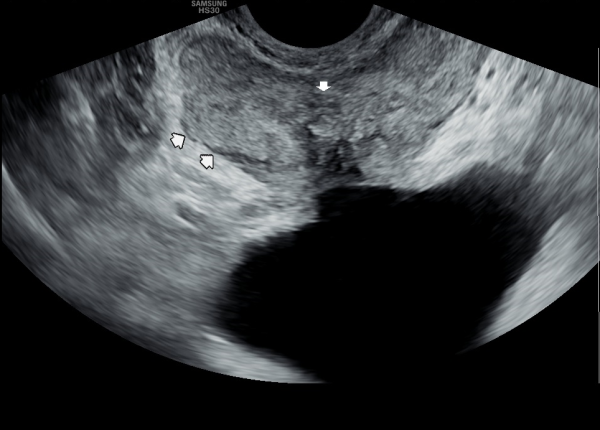

또한 방광벽이 배뇨장애로 두꺼워져 과민성 방광이 의심되는 초음파 사진입니다.

The ultrasound image also shows that the bladder wall has become thickened, likely due to urination difficulties. This may suggest an overactive bladder, which can cause frequent or urgent urination.

추적 경직장 전립선 초음파 사진상 사정관 주위에 탈락되어 막혀 있던 상피 세포가 현저히 감소하고

과민성 방광을 생기게 했던 두터운 방광벽이 감소하고 있는 사진입니다.

"This follow-up transrectal prostate ultrasound image shows a significant reduction in the accumulated exfoliated epithelial cells that had previously obstructed the area around the ejaculatory ducts, along with a noticeable thinning of the previously thickened bladder wall,

which had contributed to overactive bladder symptoms.